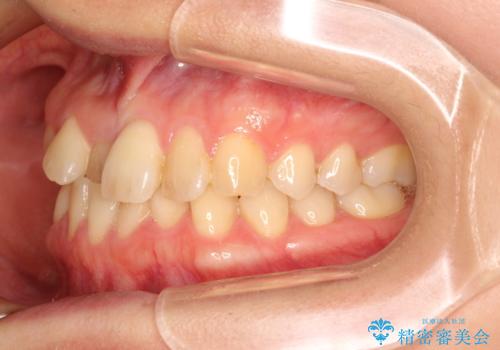

- 前歯の歯並びが気になるとのことで来院されました。

右上の1番目の歯が内側に入り込んでしまっており、その歯がの先端がすり減ってしまっていました。

インビザラインによる矯正治療で前歯の歯並びを改善し、セラミッククラウン装着により歯の形態の回復をする計画としました。

矯正とセラミックを併用することで、より完成度の高い状態に仕上げることができました。